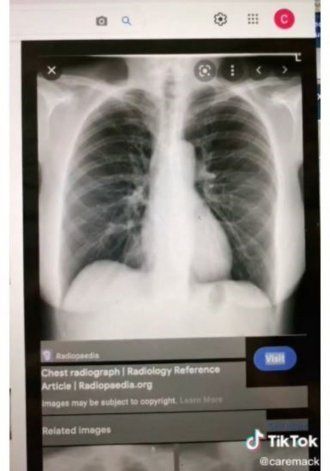

Detalló que cuando el médico la revisó, encontró que tenía una infección pulmonar la cual debía ser tratada. Pero antes de dar medicación decidió sacarle una radiografía. Siendo de esta manera, que descubrieron que tenía el corazón del otro lado del pecho.

En medio de todo, la joven pensó que todo se trataba de una broma de mal gusto, pero luego de ver la imagen quedó impactada. Ahora, esta historia de la joven Clarie Mack se hizo viral en TikTok y ahí contó su situación.

“El médico explicó que se llama dextrocardia y que debería informar a mi doctor de atención primaria sobre mi condición”.

De acuerdo a Medlineplus, la dextrocardia existe. Describen que es una condición muy poco frecuente, pero existen casos en los que el corazón aparece de lado derecho y no en el izquierdo.